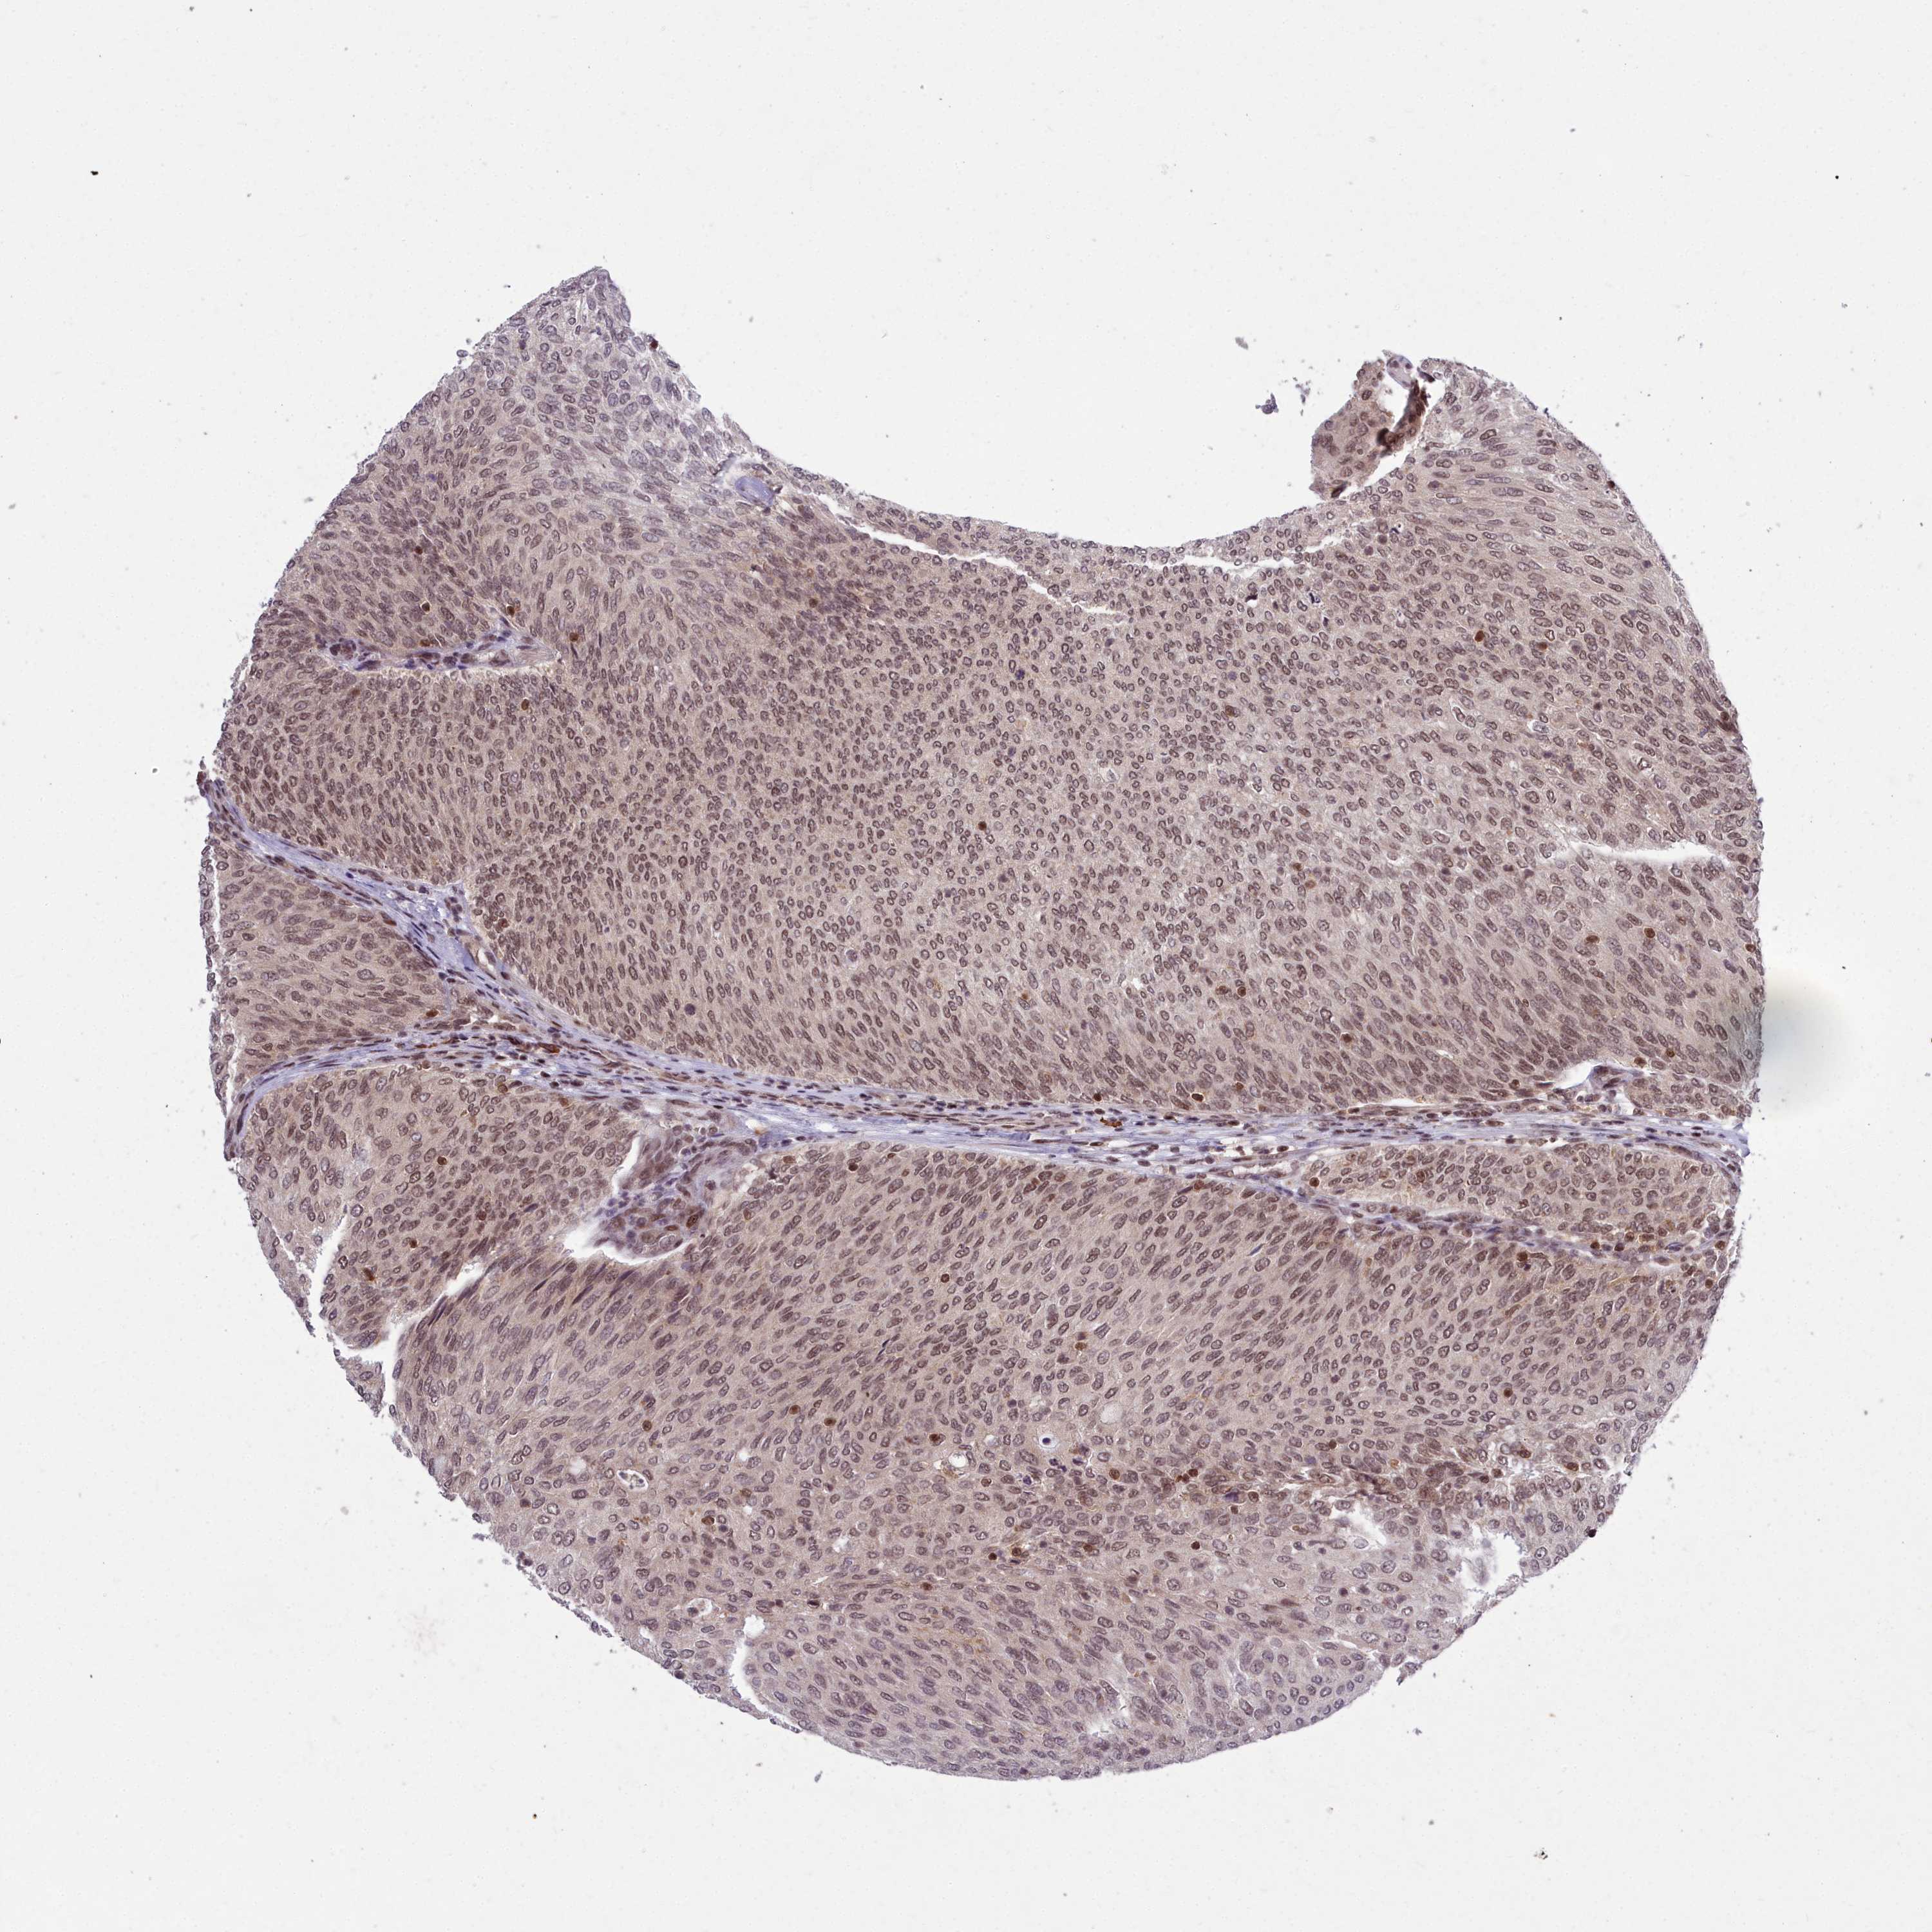

UROTHELIAL CANCER - Protein expressioni

A mouse-over function shows sample information and annotation data. Click on an image to view it in a full screen mode. Samples can be filtered based on level of antibody staining by selecting one or several of the following categories: high, medium, low and not detected. The assay and annotation is described here.

Note that samples used for immunohistochemistry by the Human Protein Atlas do not correspond to samples in the TCGA dataset.

Antibody stainingi

Antibody staining in the annotated cell types in the current human tissue is reported as not detected, low, medium, or high, based on conventional immunohistochemistry profiling in selected tissues. This score is based on the combination of the staining intensity and fraction of stained cells.

Each image is clickable and will lead to virtual microscopy that enables deeper exploration of all samples and also displays staining intensity scores, fraction scores and subcellular localization as well as patient and tissue information for each sample.

Antibody HPA044811

Staining

High

Medium

Low

Not detected

Intensity

Strong

Moderate

Weak

Negative

Quantity

>75%

75%-25%

<25%

None

Location

Nuclear

Cytoplasmic/membranous

Cytoplasmic/membranous,nuclear

Urothelial carcinoma, Low grade

Urothelial carcinoma, High grade